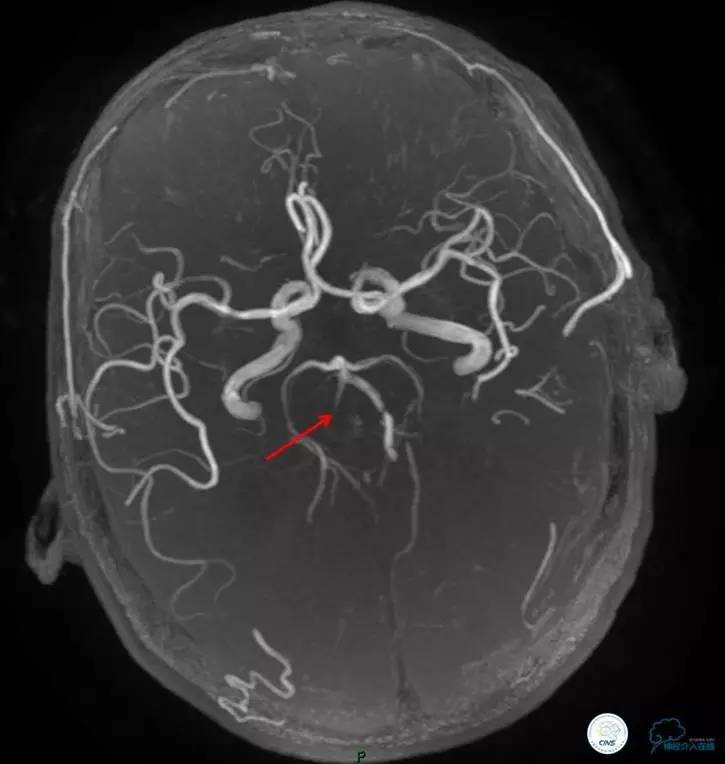

▼头颅MR

术前DSA